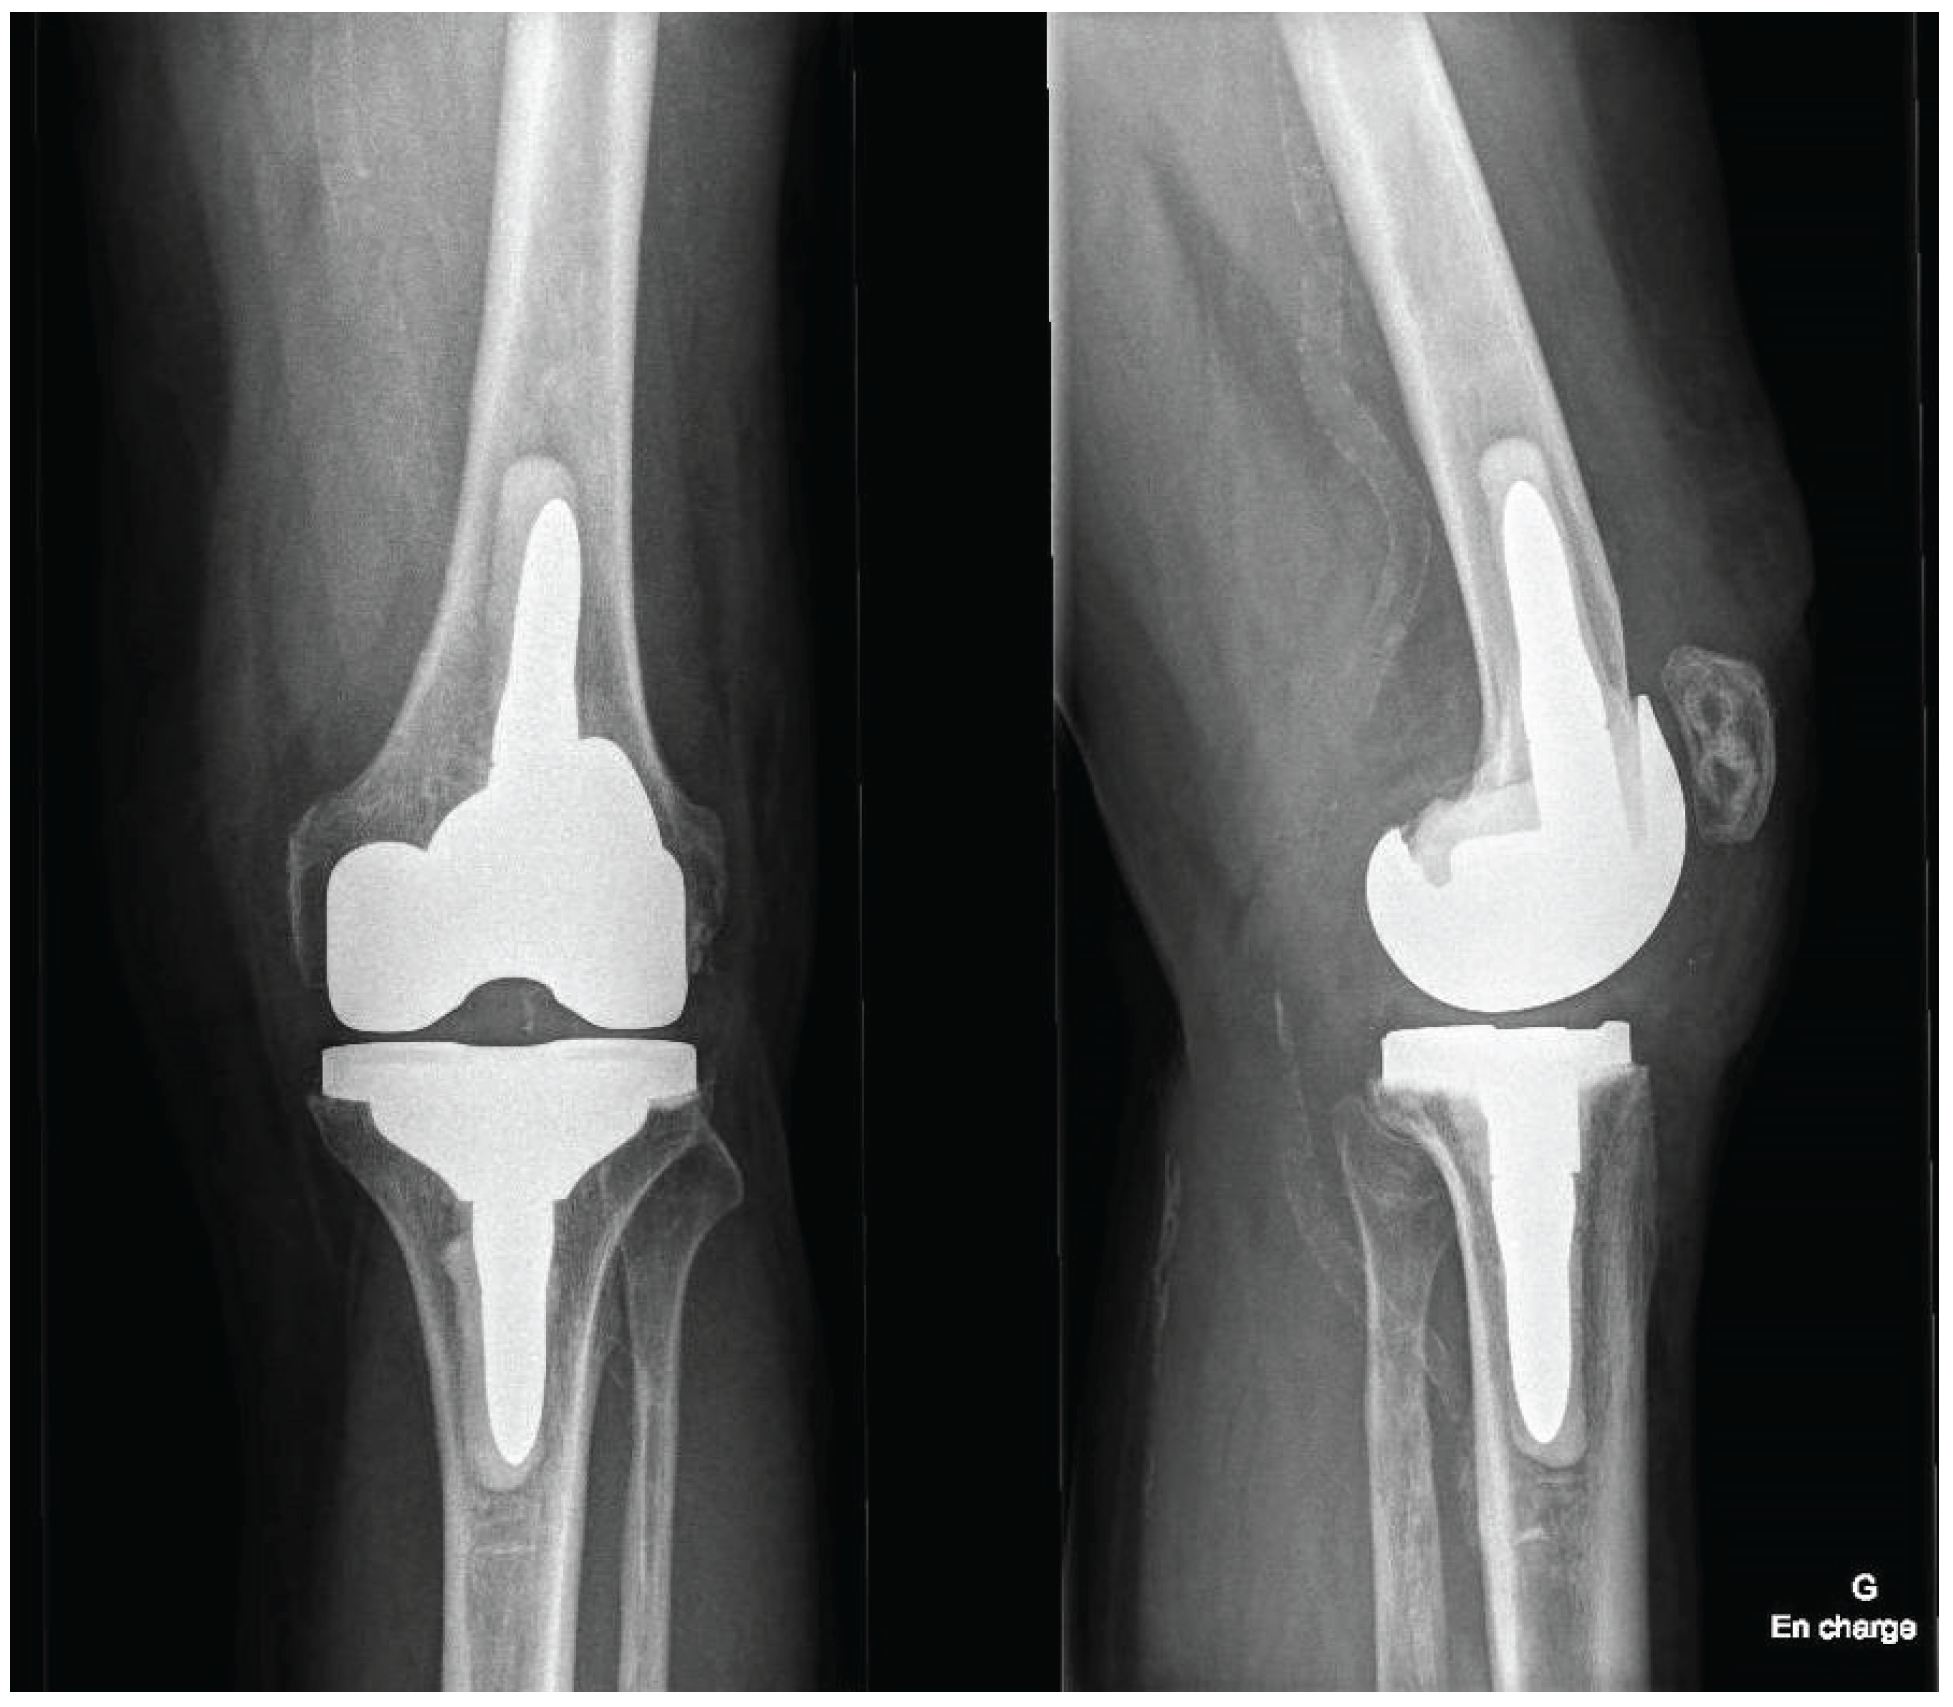

Postoperatively, patients follow a standardized rehabilitation program encouraging early mobilization and full weight-bearing as tolerated. Deep venous thrombosis prophylaxis and early quadriceps activation exercises are initiated according to institutional protocol. Postoperative radiographs of the knee and full-length lower limb are obtained to confirm accurate component positioning (Figure 7).

Figure 7. Radiographic comparison of preoperative and postoperative component positioning and alignment (a) Preop AP view; (b) Preop Lateral view; (c) Postop AP view; (d) Postop Lateral view.